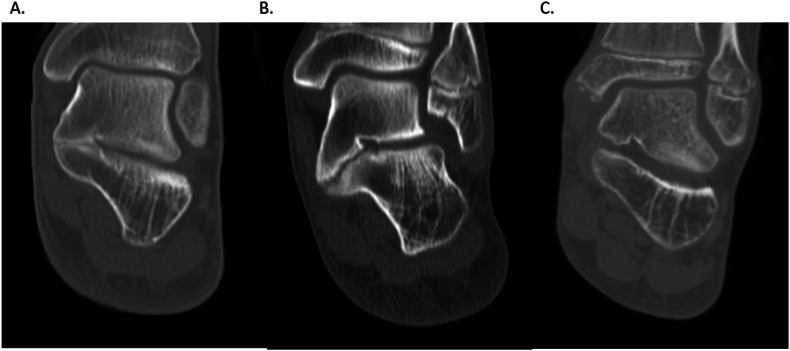

With fibrous connections, 59% of coalitions were horizontal, or parallel to the joint line (Fig. 2A). Thirty-seven percent of TCCs were medially down sloping or angulated inferiorly relative to the joint line (Fig. 2B), while 4% were medially upsloping relative to the joint line (Fig. 2C). For the sloping fibrous coalitions, bone was removed to the fibrous connection so that no small, ununited fragments were left behind at the time of surgery. It is uncertain what happens to the fibrous tissue with time following resection.

Figure 2.

A–C. The alignment of the TCC, while usually horizontal (A), may slope inferiorly relative to the joint line (B) or slope upward relative to the joint line (C). TCC, talocalcaneal coalitions.